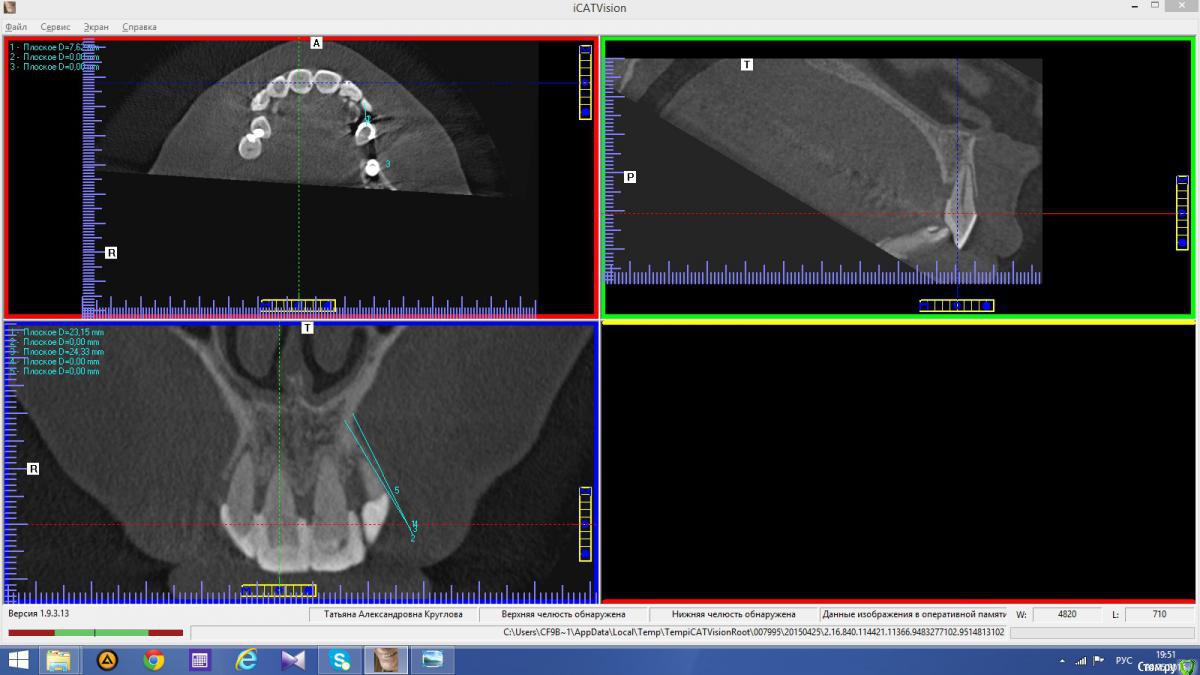

Abuk Опубликовано 24 ноября, 2015 Автор Поделиться Опубликовано 24 ноября, 2015 Снимки не могли бы показать? .все что есть готовое. Ссылка на комментарий

Abuk Опубликовано 24 ноября, 2015 Автор Поделиться Опубликовано 24 ноября, 2015 (изменено) Радикально Вы. Что оставили ей после имплантации-это инд аббатменты? На них мокап одели и нагрузили сразу? У всех был торк хороший? Или это временные абб? Что за систему использовали? В планах консоль назад, правильно я понимаю?Спасибо.увидев такую работу,сам так же подумал бы). Но там подвижность 2-3 ст. ближе к 3. Мосты болтались ,2 ки в хлам. 1 ки только стабильны. Снимал мосты,проводил кюретаж. Решил дернуть.Абатманы временные, тех. сделал на них коронки. Система анкилоз. Работа,на посл. фото, постоянная . Имплы в области 4 и по одному моляру ,консоли. Мок ап был до имплантации . По нему шаблон. Стабильность 15 -20 на 23 , остальное больше 30. Изменено 24 ноября, 2015 пользователем Abuk 1 Ссылка на комментарий